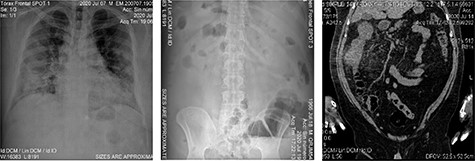

A 54-year-old male with a 2-year history of hypertension presented to the ER with dyspnea, anosmia and dysgeusia. Oxygen saturation (SatO2) was 62%, blood pressure (BP) was 149/100 mmHg and temperature was 35.6°. A detailed lab analysis is shown in Fig. 1. Due to COVID-19 suspicion, the patient was administered with paracetamol (3 g), dexamethasone (6 mg), plus oxygen therapy via mask reservoir (15 l/min). Later, he was admitted and started on high-flow oxygen therapy (Day 2), with the addition of daily enoxaparin (60 mg), baricitnab (4 mg) and methylprednisolone (80 mg). After 7 days, the patient developed severe abdominal pain localized to the iliac fossa and was referred for a surgical consultation (Day 9). A computed tomography (CT) abdomen showed hepatic steatosis without anatomical alterations in other organs. The visible portion of the thorax demonstrated a pattern of bilateral interstitial infiltrates, which is consistent with bilateral pneumonia (Fig. 2). An ultrasound (US) of the biliary ducts ruled out chronic cholecystitis or acute cholelithiasis. Three days later, the patient presented hematochezia and a reduction in hemoglobin (7.1 g/dl) (Day 12). A transfusion of packed red blood cells was started. A new abdominal US showed expansion of the ascending colon with mural engrossment without effusions. COVID-19-positive polymerase chain reaction (PCR) was reported on this same day (Day 13). A colonoscopy performed on Day 14 showed multiple ulcerations covered with fibrin (Figs 3 and 4). The patient was prepared for surgery and started on ceftriaxone (2 g) and metronidazole (1.5 g). An exploratory laparotomy performed on Day 16 revealed necrotic tissue and perforations of the ascending colon and retroperitoneal fasciitis. A right (stapled) hemicolectomy and ileostomy were completed. Vitals taken after surgery, the readings were as follows: SatO2: 80%, BP: 107/69 and temperature: 37.0°. Immediately after surgery, retroperitoneal purulent drainage was observed, which continued during his post-surgical stay. Blood work on Day 17 revealed fibrinogen and D-dimers, indicating a hypercoagulable state and signs of septic shock and neurological deterioration. After 7 days of the surgery (Day 23), the patient suffered wound dehiscence with erythematous markings and edema localized to his right flank. Blood work taken on that same day is shown in Fig. 1. A pack of red blood cells and two packs of fresh frozen plasma were transfused. Antibiotic treatment was changed to IV imipenem 2 g per day. Regrettably, the preceding interventions were not met with success, and after 28 days of hospitalization, the patient expired from sepsis-related complications. A portion of the colonic tract was preserved for histopathological analysis (Fig. 5).

Imaging studies; (A) patient’s chest X-ray with bilobular diffuse pulmonary and alveolar infiltrate along with multiple opacities are present; (B) patient’s abdominal X-ray with dilated small intestine and colon with an occlusion located at the hepatic angle; edema and abdominal air fluid levels are noted; (C) abdominal CT scan showing engrossment of the ascending colonic wall at the hepatic angle with inflammation of pericolic adipose tissue; no free air or liquids are appreciated, suggesting a colonic occlusion.